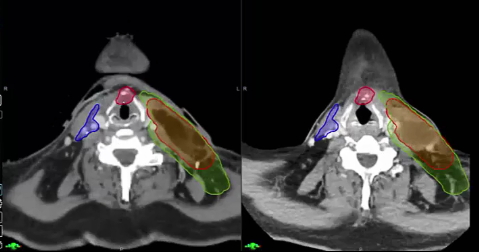

Elective Neck dose, Reirradiation, Carotid artery dose, 40Gy to neck, Pentoxyfylline and Vitamin E for neck Fibrosis, Neck failure rates, Submandibular Gland sparing, Review Dr. Sher’s plan, tongue tumor, dose versus volume, contralateral failure, oropharynx, drug trials, nasopharynx, volume desi...